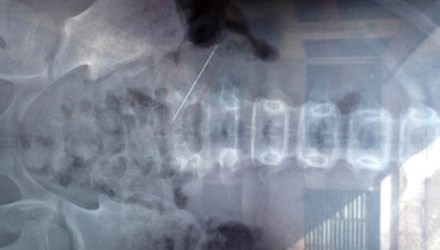

Dị vật là chiếc kim khâu nằm trong bụng bệnh nhân. Ảnh nguồn: Tiền Phong |

Qua quá trình chụp X-quang, các bác sĩ đã phát hiện một dị vật kim khí nằm trong thành bụng, sau đó họ đã nhanh chóng chuyển cô bé vào phòng phẫu thuật.

Sau 1 tiếng đồng hồ phẫu thuật, các bác sĩ đã lấy được dị vật là chiếc kim khâu ra khỏi thành bụng.